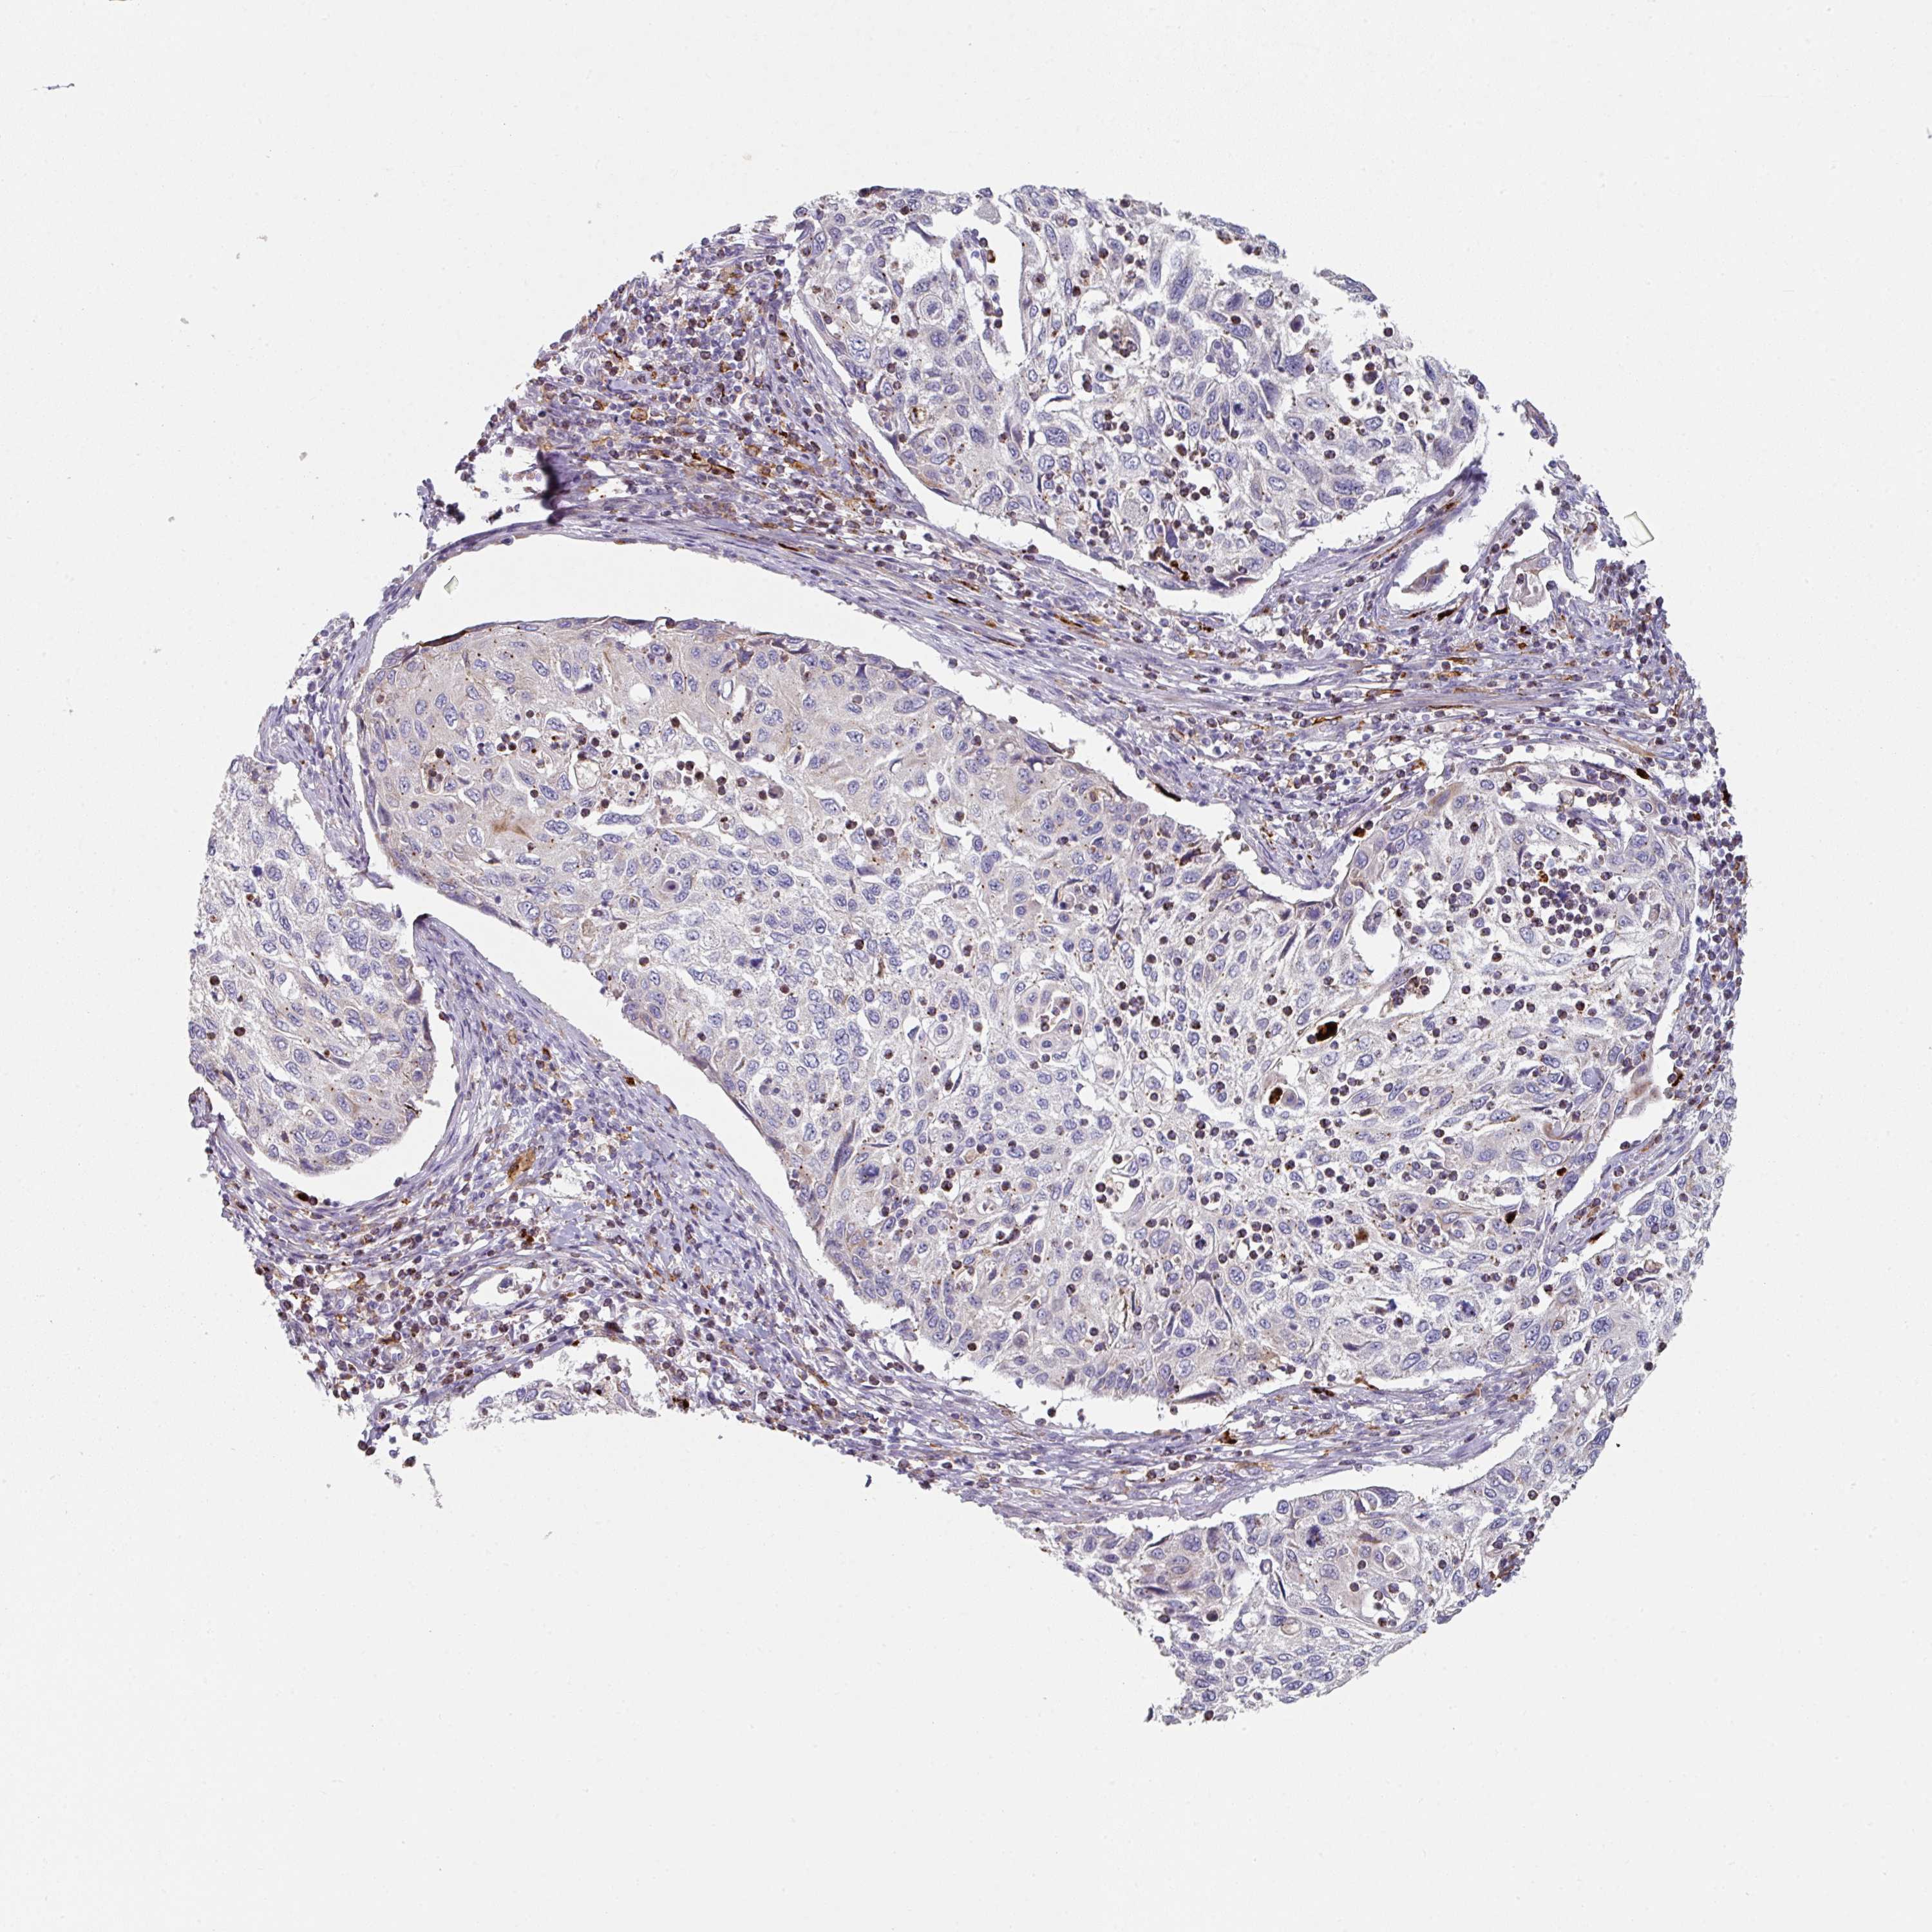

CERVICAL CANCER - Protein expressioni

A mouse-over function shows sample information and annotation data. Click on an image to view it in a full screen mode. Samples can be filtered based on level of antibody staining by selecting one or several of the following categories: high, medium, low and not detected. The assay and annotation is described here.

Note that samples used for immunohistochemistry by the Human Protein Atlas do not correspond to samples in the TCGA dataset.

Antibody stainingi

Antibody staining in the annotated cell types in the current human tissue is reported as not detected, low, medium, or high, based on conventional immunohistochemistry profiling in selected tissues. This score is based on the combination of the staining intensity and fraction of stained cells.

Each image is clickable and will lead to virtual microscopy that enables deeper exploration of all samples and also displays staining intensity scores, fraction scores and subcellular localization as well as patient and tissue information for each sample.

Antibody HPA052606

Antibody HPA077139

Staining

High

Medium

Low

Not detected

Intensity

Strong

Moderate

Weak

Negative

Quantity

>75%

75%-25%

<25%

None

Location

Nuclear

Cytoplasmic/membranous

Cytoplasmic/membranous,nuclear

Squamous cell carcinoma, NOS

Adenocarcinoma, NOS